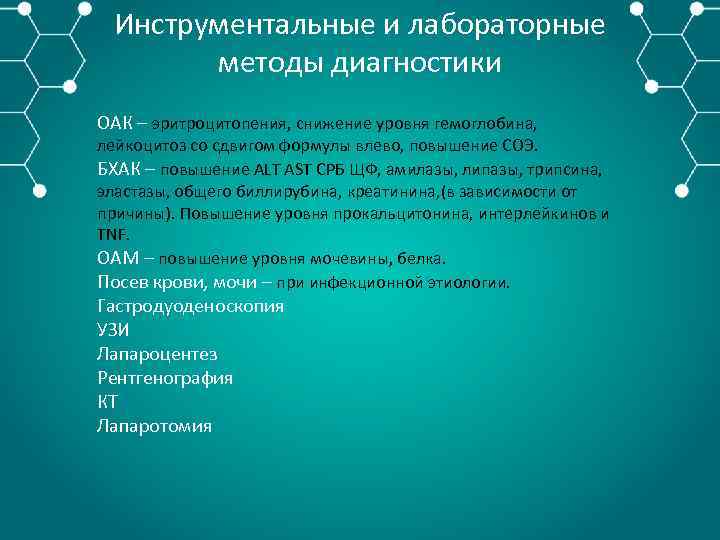

Инструментальные и лабораторные методы диагностики ОАК – эритроцитопения, снижение уровня гемоглобина, лейкоцитоз со сдвигом формулы влево, повышение СОЭ. БХАК – повышение ALT AST СРБ ЩФ, амилазы, липазы, трипсина, эластазы, общего биллирубина, креатинина, (в зависимости от причины). Повышение уровня прокальцитонина, интерлейкинов и TNF. ОАМ – повышение уровня мочевины, белка. Посев крови, мочи – при инфекционной этиологии. Гастродуоденоскопия УЗИ Лапароцентез Рентгенография КТ Лапаротомия